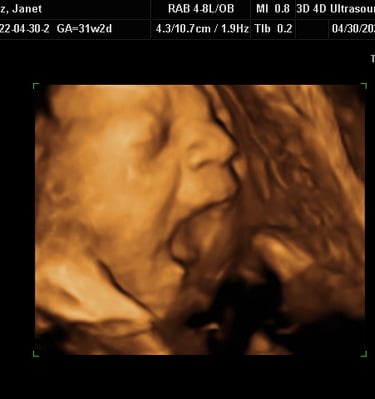

Our Gallery

Explore beautiful moments captured during our 3D and 4D sessions.